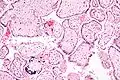

![]() Micrografía de citomegalovirus (CMV) infección de la placenta (placentitis CMV), una infección de transmisión vertical: El característico gran núcleo de una célula infectada con CMV se ve descentrada en la parte inferior derecha de la imagen, tinción H&E. | ||

Además de infectar al feto, los patógenos transplacentarios pueden causar placentitis (inflamación de la placenta) y/o corioamnionitis (inflamación de las membranas fetales).

Placentitis por citomegalovirus (CMV)